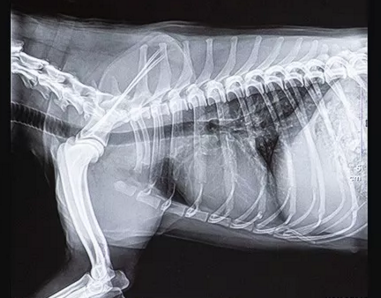

寵物dr拍攝效果圖